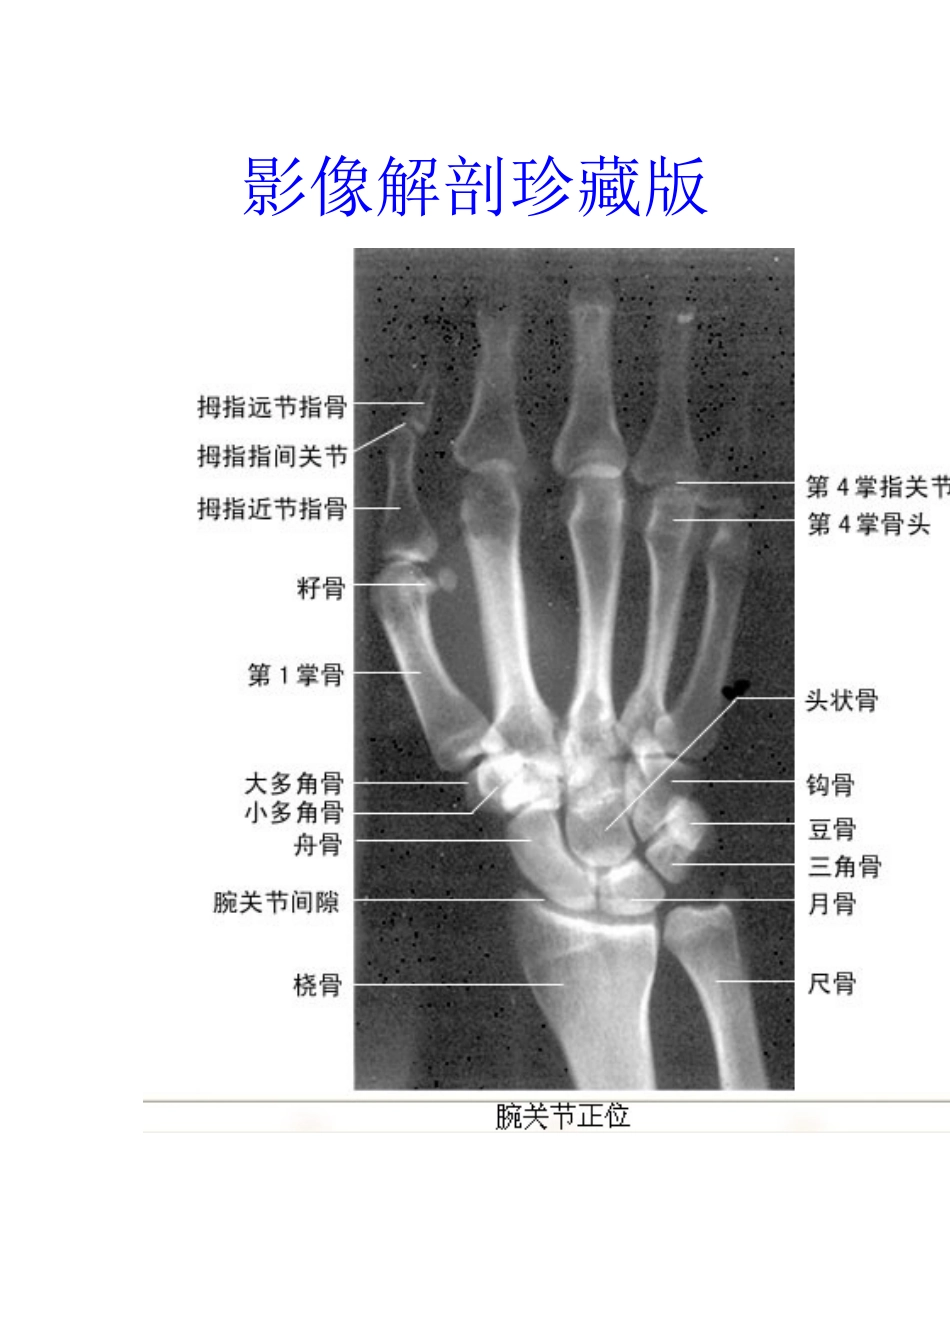

影像解剖珍藏版VIP免费